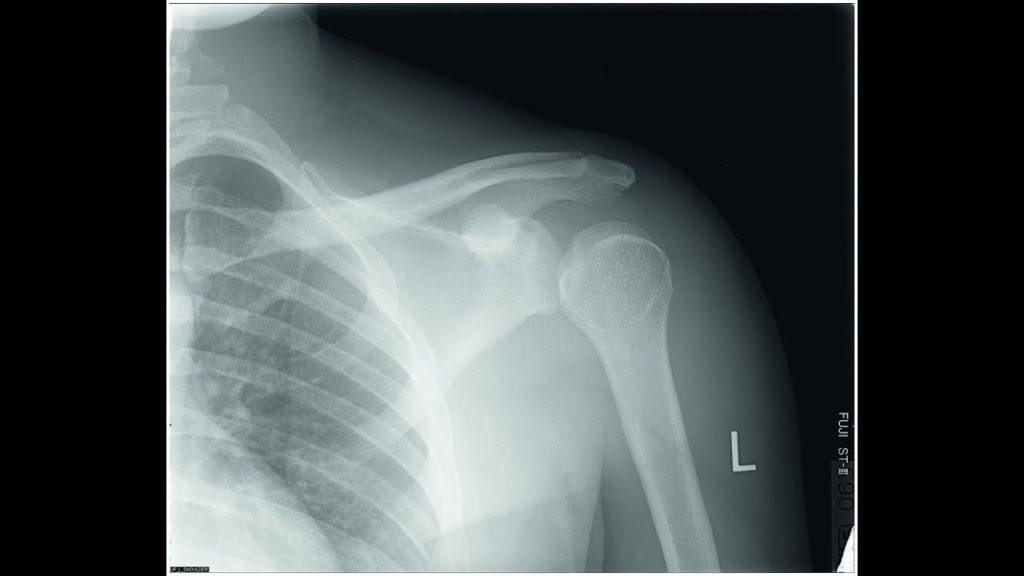

Eine Schultersubluxation bei Hemiplegie ist die teilweise Ausrenkung des Schultergelenks nach einem Schlaganfall, die durch die Lähmung der Armmuskulatur und Schwerkraft verursacht wird. Sie ist eine häufige Komplikation, die zu Schmerzen und Bewegungseinschränkungen führt und die Rehabilitation erschwert.

- Sichtbare Fehlstellung des Oberarmkopfes